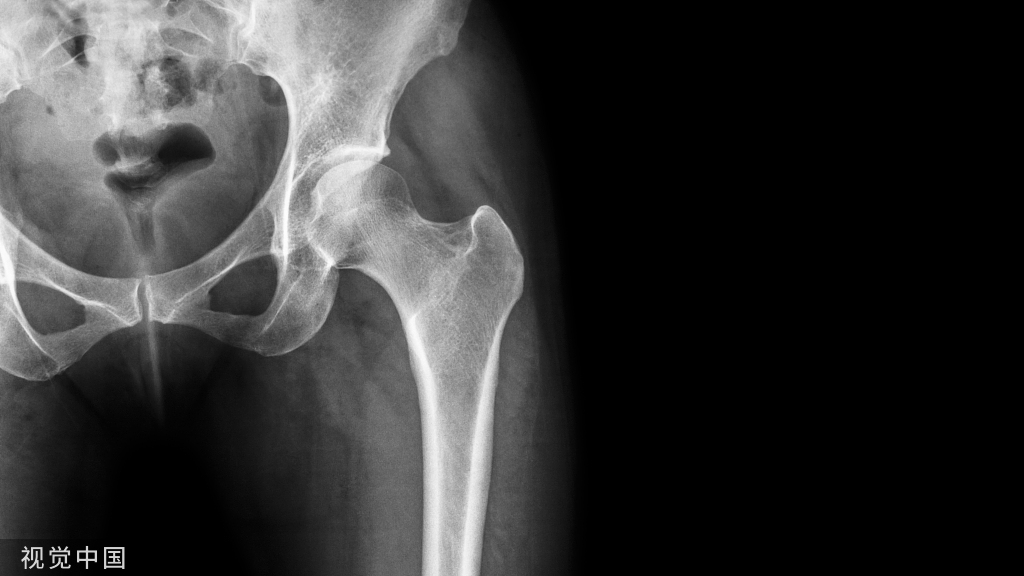

骨质疏松症(osteoporosis)是一种以骨量低下、骨组织微结构损坏,导致骨脆性增加,易发生骨折为特征的全身性骨病。2001年美国国立卫生研究院(National Institutes of Health,NIH)将其定义为骨强度下降和骨折风险增加为特征的骨骼疾病。骨质疏松症可发生于任何年龄,但多见于绝经后女性和老年男性。

骨质疏松症的发病机制非常复杂,总体上,是遗传因素和非遗传因素相互作用的结果。依据病因,骨质疏松症分为原发性和继发性两大类。

• 原发性骨质疏松症包括:绝经后骨质疏松症(Ⅰ型)、老年骨质疏松症(Ⅱ型)和特发性骨质疏松症(青少年型)。

①绝经后骨质疏松症一般发生在女性绝经后 5~10 年内;②老年骨质疏松症一般指 70 岁以后发生的骨质疏松;③特发性骨质疏松症主要发生在青少年,病因尚未明。